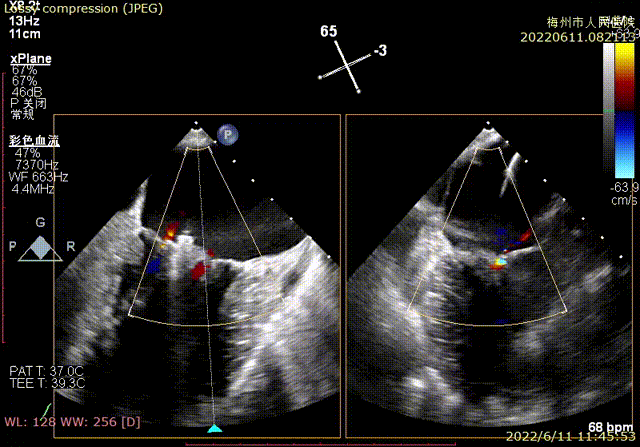

经食道超声显示(术前):二尖瓣前叶长度32mm,后叶长度19mm,脱垂高度10mm,脱垂宽度为11mm,VC3.2mm, MVA 4.0cm²。

术前TEE显示二尖瓣重度反流,反流位置位于A2/P2区